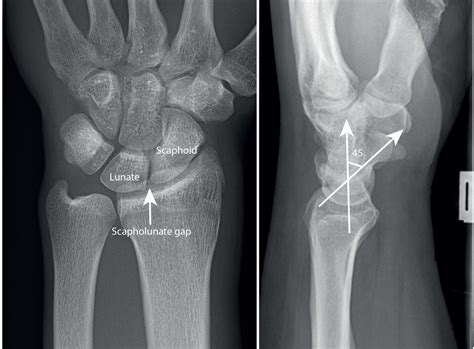

Suffering from a ligament tear of the wrist? Learn about common causes, painful symptoms, and effective treatment options. From physical therapy to surgical repair, discover how to manage wrist instability and restore joint function. Get expert guidance on recovery timelines and exercises to regain strength and mobility after a severe wrist sprain or ligament injury.